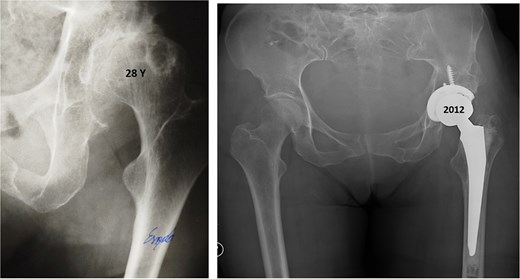

Twenty-eight years after triple osteotomy, the patient presented with painful end-stage osteoarthritis, with body mass index of 18. A hybrid cemented THA was performed using a standard posterolateral approach (Fig. 3). A cobalt-chrome femoral head was articulated with highly reticulated polyethylene liner. A press-fit cementless cup stabilized with two screws (Tylogy®, Zimmer) and a cemented straight femoral stem (Müller®, Zimmer) were implanted.

Anteroposterior radiographs of the pelvis 28 years after the pelvic osteotomy, showing advanced left hip osteoarthritis (Tönnis Grade V). A hybrid cemented total hip arthroplasty was implanted using a standard posterolateral approach.